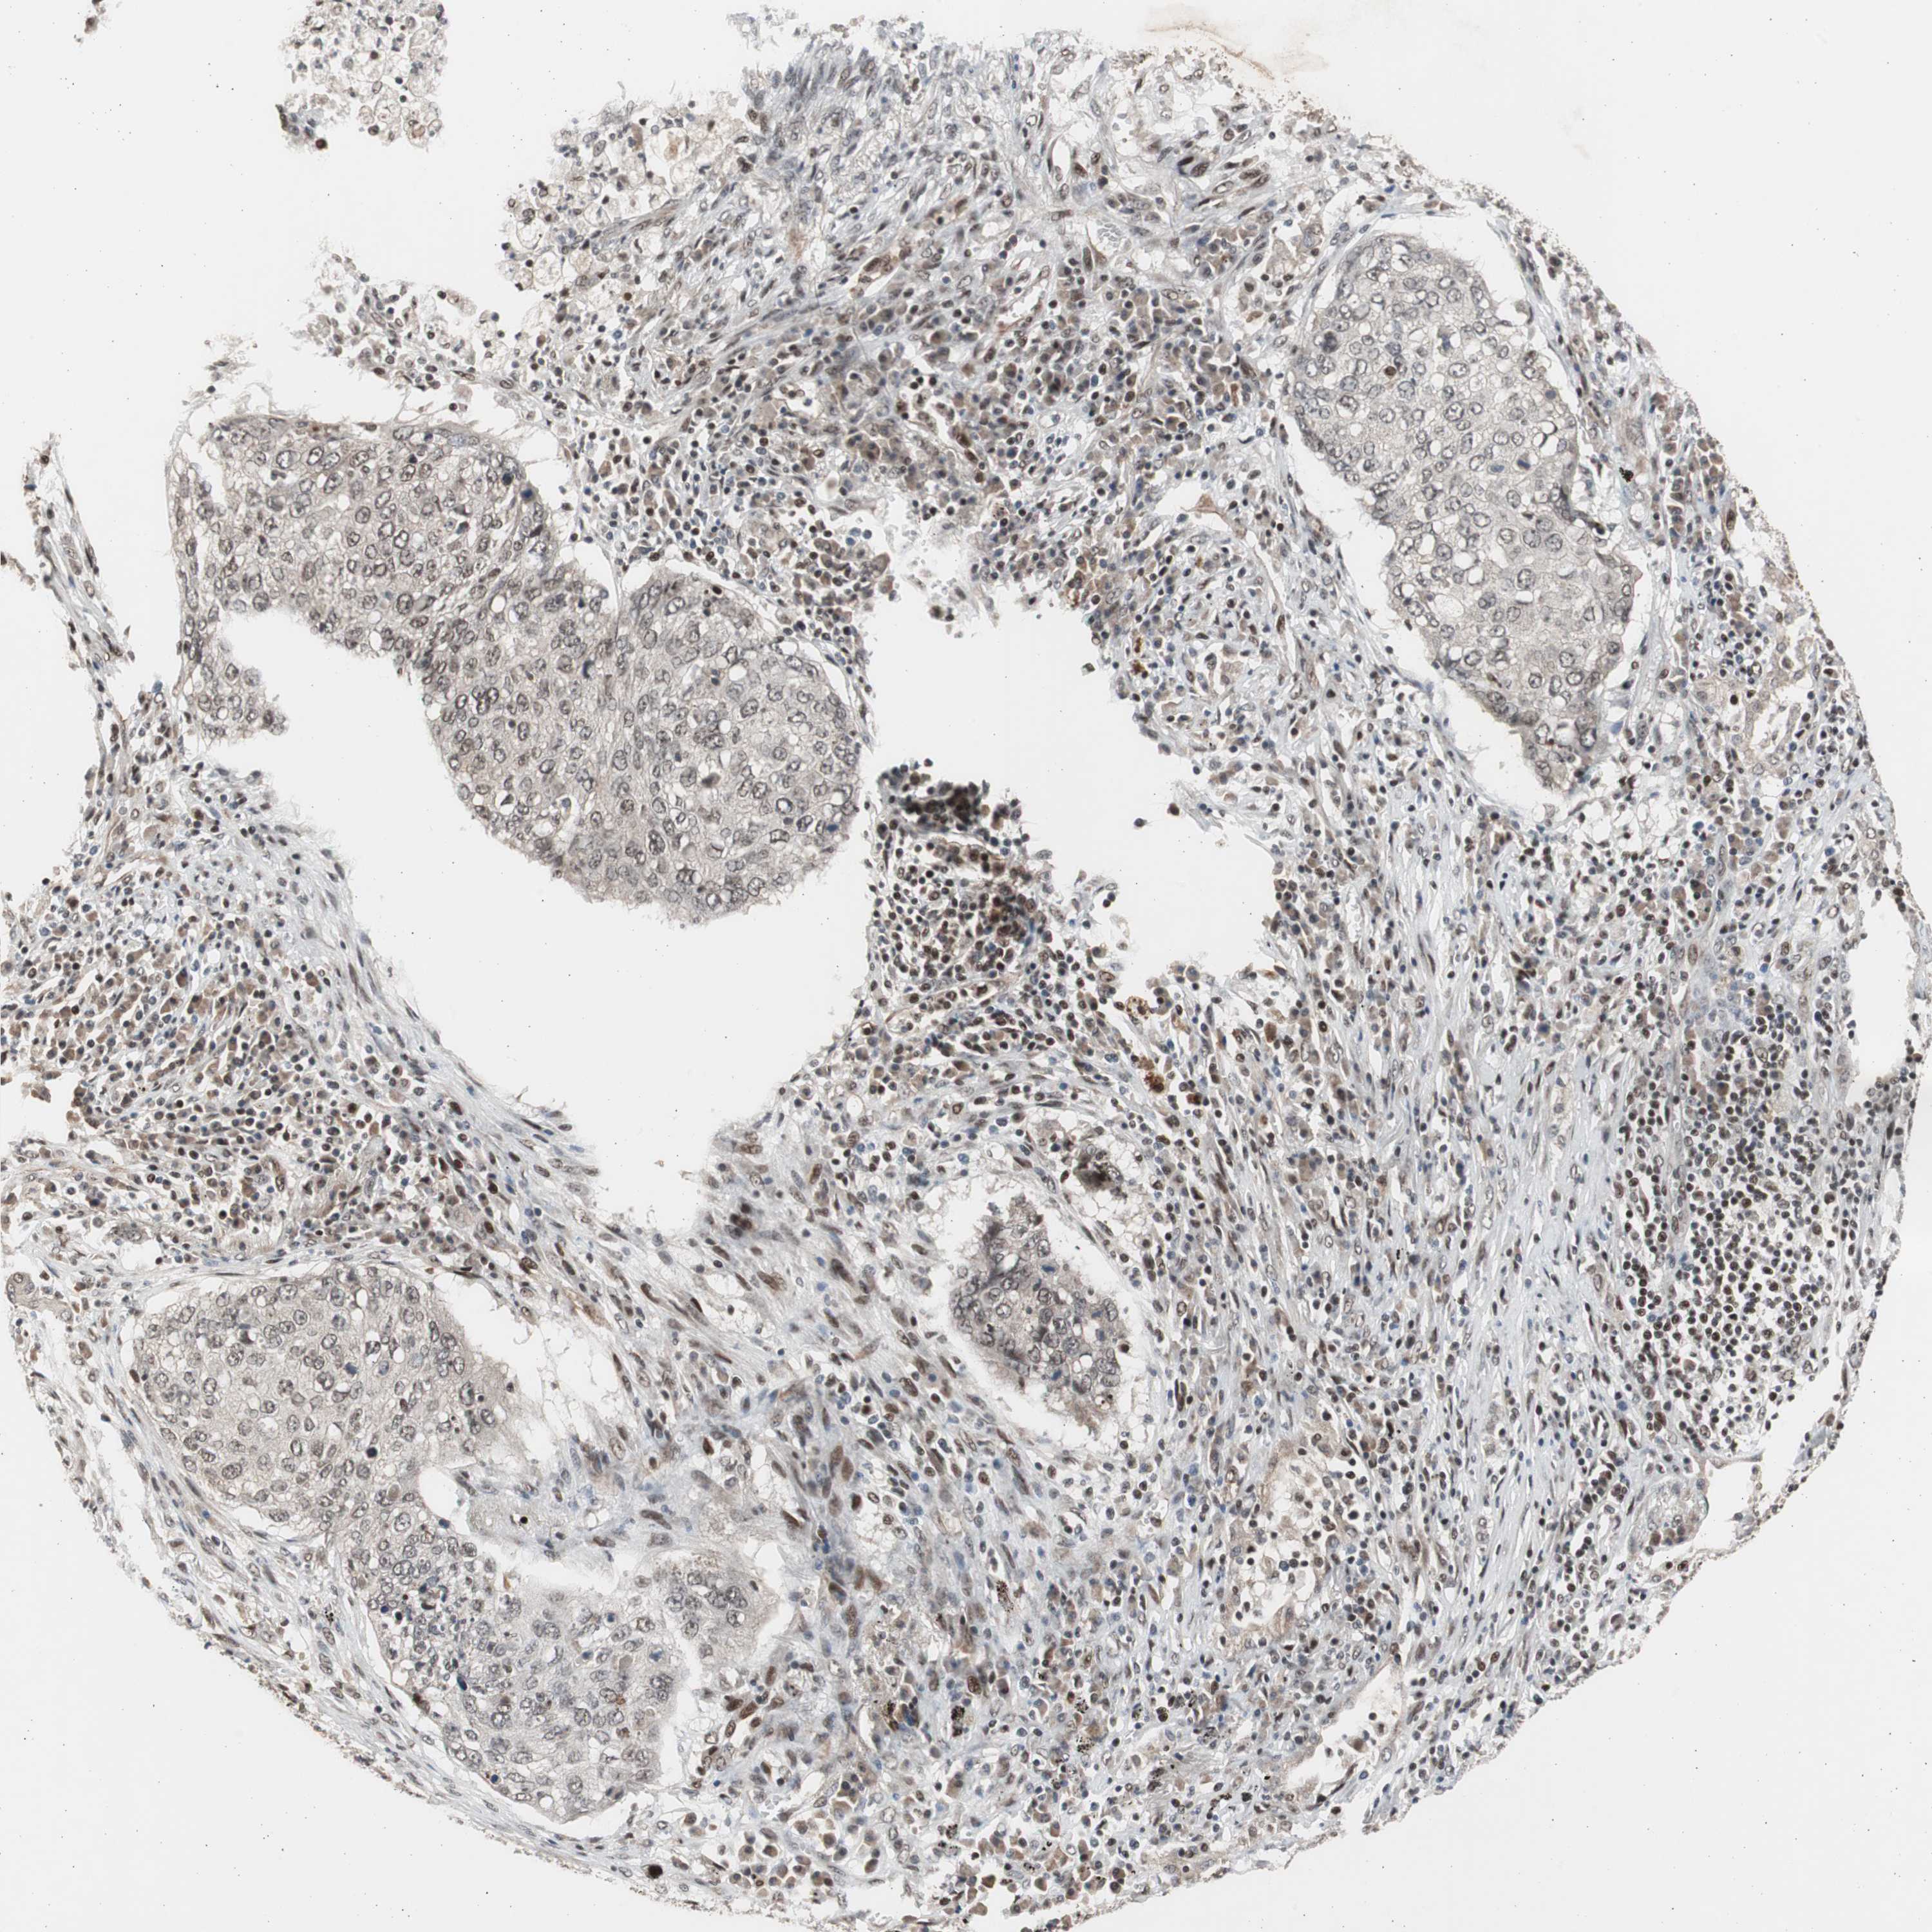

CANCER LUNG CANCER Show tissue menu